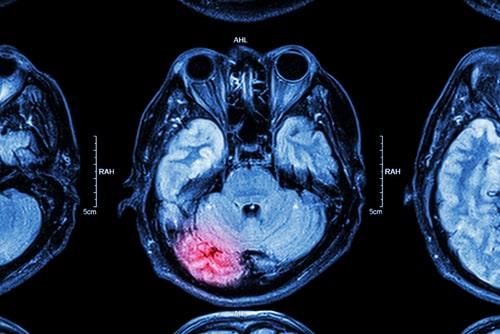

CT injury lawyerHead injuries can range from fairly minor to catastrophic. Some types of head injuries sustained in accidents can be life-altering. Traumatic brain injuries may impact a person’s cognitive or physical ability for the rest of her life. Some people who have suffered these injuries will require permanent round-the-clock care in a skilled nursing facility or from a home health aid. Others will never be able to return to their careers or finish school. Less serious head injuries might be serious but not catastrophic. If you sustained any type of head injury due to an accident caused by another party’s negligence, you should consult a Greenwich, CT catastrophic injuries lawyer immediately. You may be entitled to significant compensation.